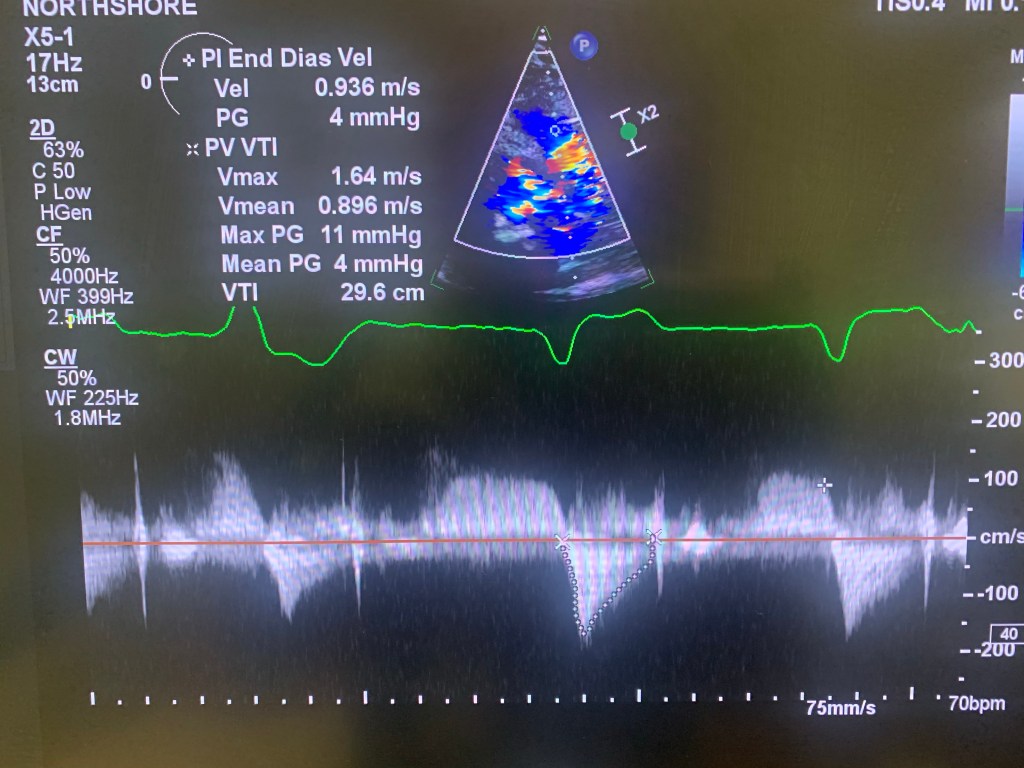

Adults with this condition don’t need surgical intervention (most of the time). However, adults with a repaired TOF, the VSD patch is evident on echo, aortic root is enlarged and there’s so evidence of residual RV outflow obstruction. The major issue is late pulmonic regurgitation.

During echo, make sure to get a good view of the aorta and the aortic root. Measure in parasternal long axis view. If possible, obtain a few extra images. Use pulsed or CW Doppler signal to look for diastolic reversal of flow equal in signal strength to antegrade flow (pulmonic regurgitation). Obtain a good RV images (RV focused view) and make sure to see the endocardium well. If the patient had a VSD repair, obtain extra images in A4 and Sub4 at the level of ventricular septum. Use PW and CW in Sub4 to make sure there’s no leakage after the repair.